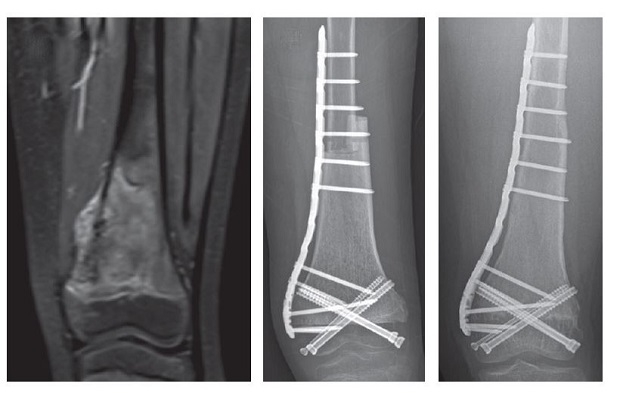

수술 전 무릎 골육종 환자의 자기공명영상(MRI·왼쪽)과 수술 직후(가운데)와 수술 후 4년째의 단순 방사선사진. 종양을 제거한 부위는 골이식을 통해 개건했고 수술 후 무릎관절 운동은 정상에 가깝게 회복됐다.

연구팀은 수술 전 항암치료 효과가 좋은 환자를 대상으로, 관절을 구성하는 뼈 부분은 보존하면서도 종양이 있는 뼈 부분만 제거했다. 종양이 있던 위치는 조직기증으로 확보한 타인의 뼈를 이식해 개건(改建)했다.